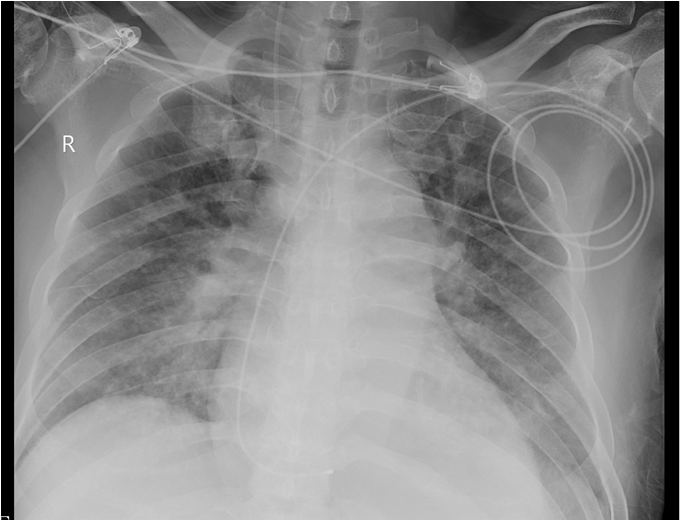

5.27及6.1查胸片示:双肺肺水肿,双侧大量胸腔积液,明显进展